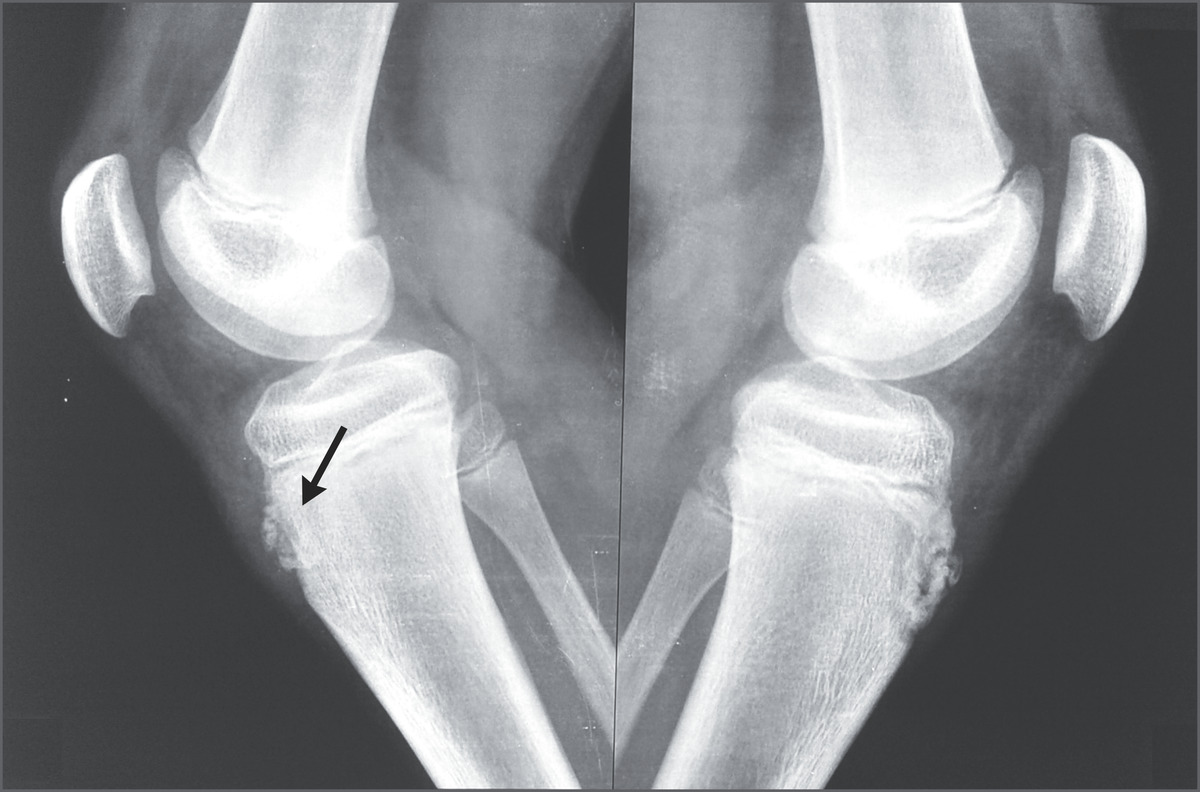

Chụp X-quang đầu gối.

Click vào ảnh để xem 4 hình ảnh minh họa